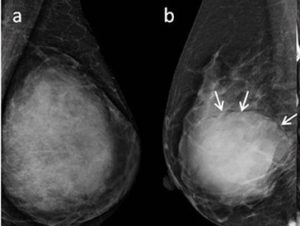

To distinguish between the diagnosis of phyllodes and fibroadenoma, doctors will perform specific tests to confirm, along with a clinical breast exam. The size and shape of the lump are checked with this clinical exam. The tests for diagnosis might include:

- The pictures of breasts are taken by mammogram which uses X rays